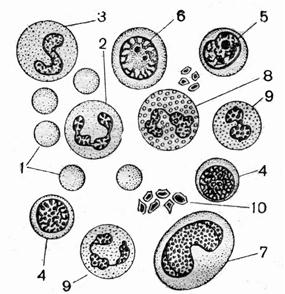

Эритроциты вследствие значительного численного преобладания занимают почти все поле зрения (Рис. 61). Зрелые эритроциты не способны к синтезу нуклеиновых кислот и гемоглобина.

Рис. 61. Мазок крови человека: 1- эритроциты; 2 – нейтрофилы; 3 – палочкоядерные нейтрофилы, малые лимфоциты; 5 – средние лимфоциты; 6 – большие лимфоциты; 7 – моноциты; 8 – эозинофилы; 9 – базофилы;10 - кровяные пластинки

На предметном стекле выглядят круглыми с более светлой, чем по краям, средней частью. Лейкоциты имеют шаровидную форму. Большинство лейкоцитов крупнее эритроцитов и всегда содержат ядро. Чаще остальных форм встречаются сегментоядерные нейтрофилы. Ядра нейтрофилов разделены перетяжками на сегменты и часто располагаются эксцентрично.

Кроме эритроцитов на мазке крови встречаются лейкоциты: среди них эозинофилы – округлые клетки по величине превышающие эритроциты, с 3 – 4 сегментным плотным ядром и ярко-оранжевой зернистостью в цитоплазме. Часто попадается и другая разновидность лейкоцитов – лимфоциты. Это округлые клетки, более мелкие, чем эозинофилы и эритроциты, с плотным округлым ядром и узкой каймой голубой (базофильной) цитоплазмы. Часто эти клетки имеют короткие, неправильной формы псевдоподии.

Большинство клеток мазка принадлежит эритроцитам. Они имеют овальную форму и овальное плотное ядро, интенсивно окрашивающееся гематоксилином в сине-фиолетовый цвет. Цитоплазма этих клеток закрашивается эозином в оранжево-красный цвет за счет гемоглобина, растворенного в теле этой клетки.

Примером клеток, расположенных по отдельности и имеющих округлую или овальную форму, могут быть клетки крови лягушки (Рис. 60).